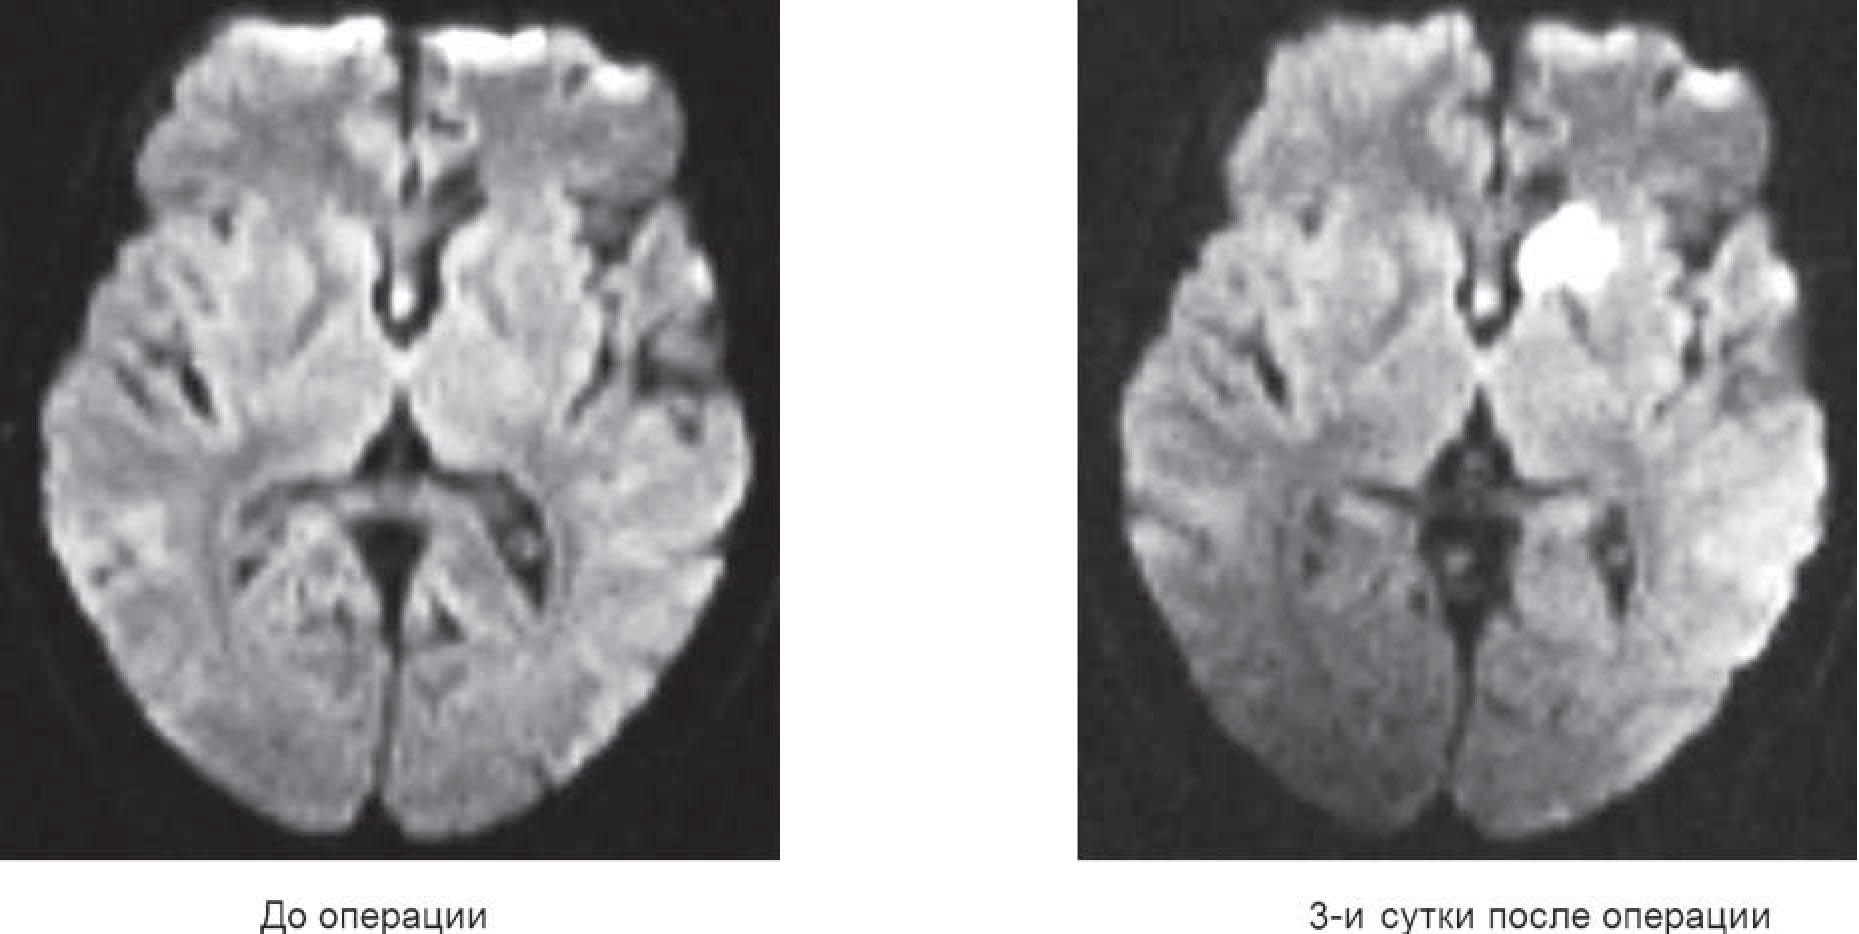

Результаты нейропсихологического обследования пациентов до и после операции свидетельствуют об ухудшении высших психических функций в послеоперационном периоде. Так, медиана (Me) методики MoCA до операции составила 28 баллов, после операции – 27,5 балла, T-критерий Уилкоксона – 27,5 (Z=2,94; p=0,036). При этом значимой динамики данного показателя в группе внутрисосудистого лечения не отмечено (MeДО=28 баллов, MeПО=27,5 балла, T=14; Z=0,56; p=0,57). У пациентов, перенесших микрохирургические операции, ухудшение результатов обследования было значимым (MeДО=27,5 балла, MeПО=26 баллов, T=4; Z=2,02; p=0,043). У 6 (45%) пациентов очаги ишемического повреждения локализовались в области подкорковых ганглиев, у двоих больных – в полушариях мозжечка, по одному наблюдению – при расположении в лобной и островковой доле, а также в таламусе (рис 1).

Рис. 1. МР-томограммы головы в динамике до и после внутрисосудистого вмешательства